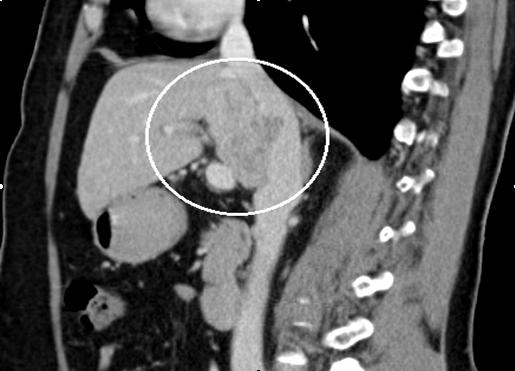

Pacienta a fost o femeie de 50 de ani. Aceasta a fost diagnosticată cu o tumoare masivă hepatică, preponderent S I, cu invazia venei cave inferioare porțiune retrohepatică și prezența simptomelor pozitive caracteristice sindromului de ocluzie a venei cave inferioare. La internare, femeia acuza dureri moderate în regiunea lombară, edeme și pastozitate a membrelor inferioare. Diagnosticul preoperator a fost stabilit pe baza investigatii CT cu contrastare in regim angiografic. Până acum așa amplasare a tumorii a fost considerată inoperabilă. Potrivit prof. univer., dr. Adrian Hotineanu, până acum acești pacienți erau refuzați pentru tratament radical și primeau doar îngrijiri paliative fără efect, care duceau inevitabil la deces. Medicul a menţionat că “toate acestea pot fi depășite doar prin tratament radical, prin rezecția hepatică cu tumoare și rezecția venei magistrale. Numai această metodă este potențial curativă și poate oferi vindecare”.

Astfel, pentru a salva viaţa pacientei, doctorii au rezecat o parte de ficat, purtător de tumoare, au mobilizat şi lanțuit porțiunea retrohepatică a venei cave inferioare. Ulterior s-a rezecat în bloc cu tumoare, care s-a înlocuit cu proteză vasculară. Medicii spun că perioada postoperatorie decurge favorabil. La moment pacienta se simte bine şi se pregatește pentru externare.